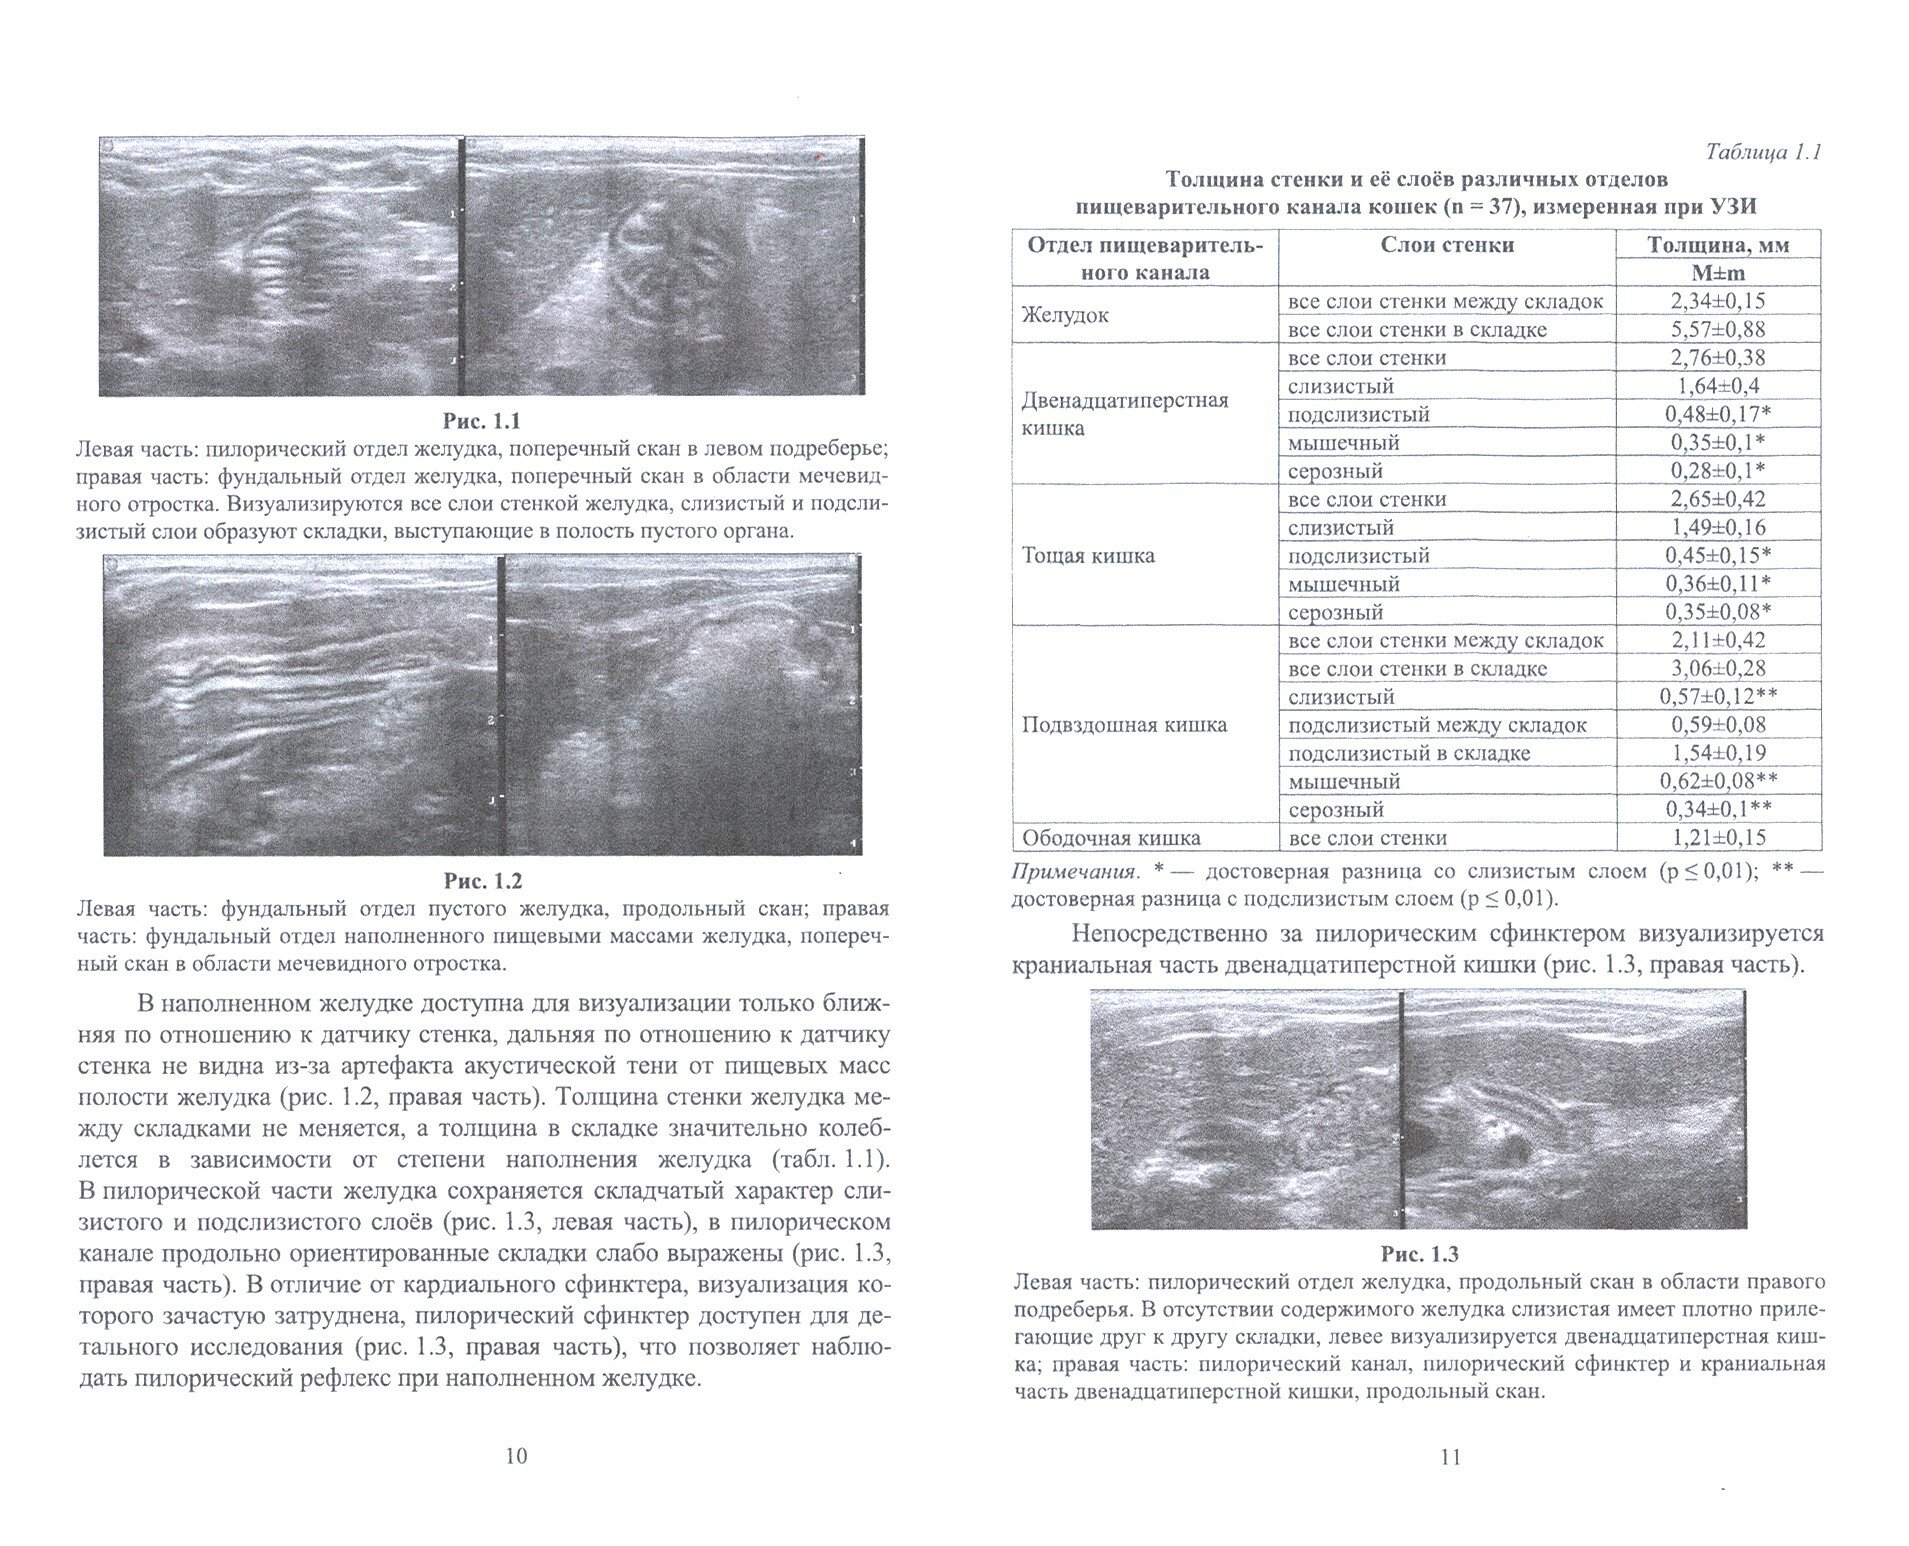

Монография посвящена описанию морфометрических и эхографических характеристик пищеварительного канала собак и кошек при транскутанном ультразвуковом исследовании. Приведены метрические показатели слоев стенки различных отделов пищеварительного канала. Впервые описана количественная характеристика эхогенности слоев стенки желудка и тонкого кишечника у собак и кошек и их соотношение. Охарактеризована эхогенность слоев стенки тонкого отдела кишечника у собак и кошек натощак и в различные временные интервалы постпрандиального периода. Определен коэффициент эхогенности двенадцатиперстной, тощей и подвздошной кишок, позволяющий проводить объективную оценку стенки кишечника с учетом вариабельности настроек различных сканеров. Описаны эхографическое проявление и локализация артефактов у собак и кошек при сканировании пищеварительного канала в режиме серой шкалы: акустической тени, реверберации, "хвоста кометы", дистального псевдоакустического усиления сигнала; в режиме цветного допплеровского картирования - артефакта движения.